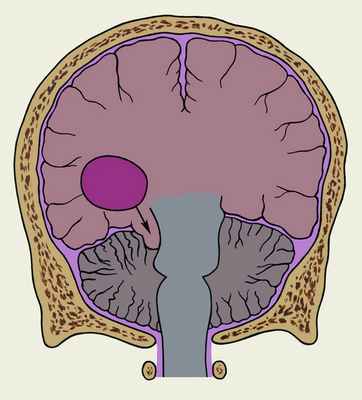

Дислокация головного мозга может сопровождаться опущением и ущемлением миндалин мозжечка в большом затылочном отверстии и верхней части позвоночного канала с развитием опасного для жизни синдрома затылочного вклинения (рис. 1). Он характерен для опухолей задней черепной ямки, однако может развиться и при опухолях, расположенных выше намета мозжечка. Клиническая картина при этом синдроме обусловлена прежде всего сдавлением продолговатого мозга и связанным с этим нарушением жизненно важных функций. При затылочном вклинении резко усиливается головная боль, особенно в затылочной области; отмечаются рвота, головокружение, увеличивающееся при изменении положения головы и тела, вынужденное положение головы, способствующее уменьшению головной боли, менингеальный синдром, поперхивание при приеме жидкой пищи, икота, усиленное потоотделение, нарастание нарушения ритма дыхания (аритмичное, прерывистое, типа Чейна — Стокса) и деятельности сердечно-сосудистой системы. Выражены симптомы внутричерепной гипертензии (см. Гипертензия внутричерепная) — прогрессирующая заторможенность, застойные диски зрительных нервов, диплопия, снижение роговичных рефлексов, обоняния, слуха и др. Быстрое нарастание явлений вклинения приводит к развитию комы и остановке дыхания.

Рис. 1. Схематическое изображение фронтального разреза головы при синдроме затылочного вклинения, обусловленном опухолью мозжечка: стрелка, идущая от опухоли, показывает направление вклинения миндалин мозжечка.